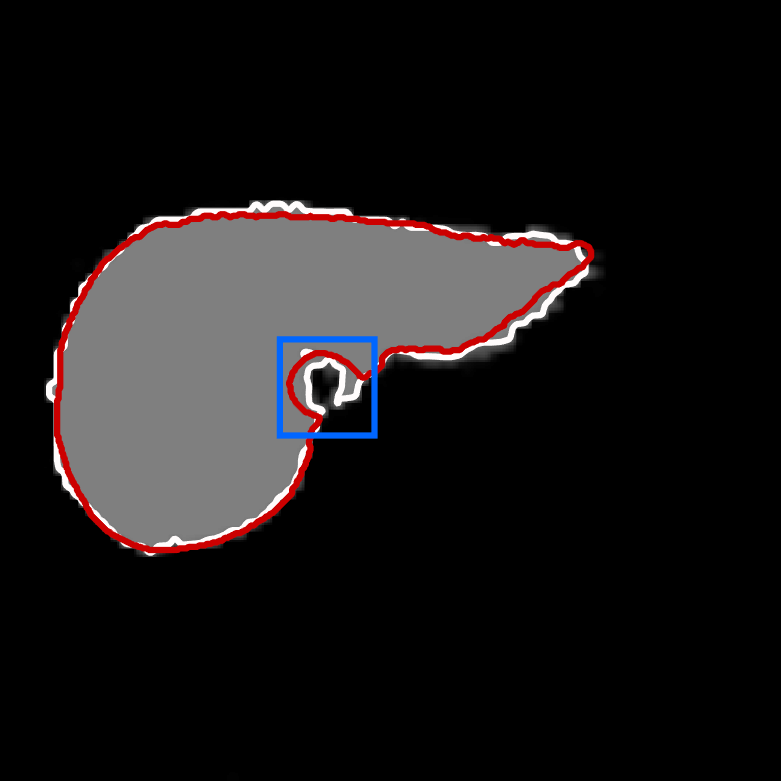

Figure 1 shows the results of the four individual segmenters. The grey level intensity reflects the probability map of foreground versus background. The white contour is the proposed segmentation boundary obtained by thresholding the probability map at 0.5. The red contour is the ground truth. 999The image for this example is slide 11 from the data of patient number 4 in the CHAOS dataset.

| U-net | Deepmedic |

|

|

| V-net | Dense V-networks |

|

|

In order to show the advantage of the ensemble, we chose a small, notoriously difficult, region to zoom on: vena cava superior (the blue rectangle in the U-Net plot in Figure 1). Figure 2 contains five plots of the segmented region. The product combiner was chosen for the ensemble. The ground truth is shaded in blue in the ensemble plot, and in red in the plots for the individual segmenters. The guessed segmentation is overlaid in transparent grey. The Dice score for the chosen area is shown under each plot. A Dice score of 1 indicates perfect segmentation while lower values indicate mismatch. As the results show, both visually and through the numbers, the ensemble segmentation is better than any of the individual ones.